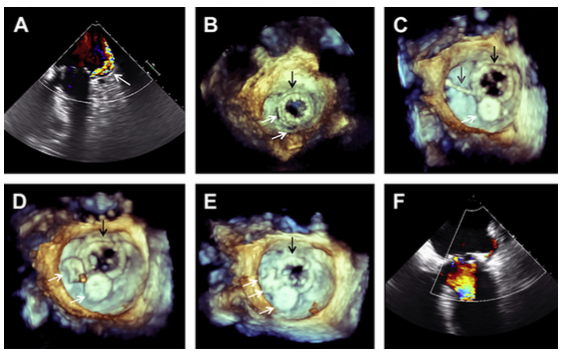

O implante valvar transcateter tem revolucionado o tratamento de pacientes com estenose aórtica severa e que possuem elevado risco para…

Exames de imagem são essenciais no planejamento, execução e acompanhamento de procedimentos cardíacos. Eles possibilitam a obtenção de dados morfológicos…